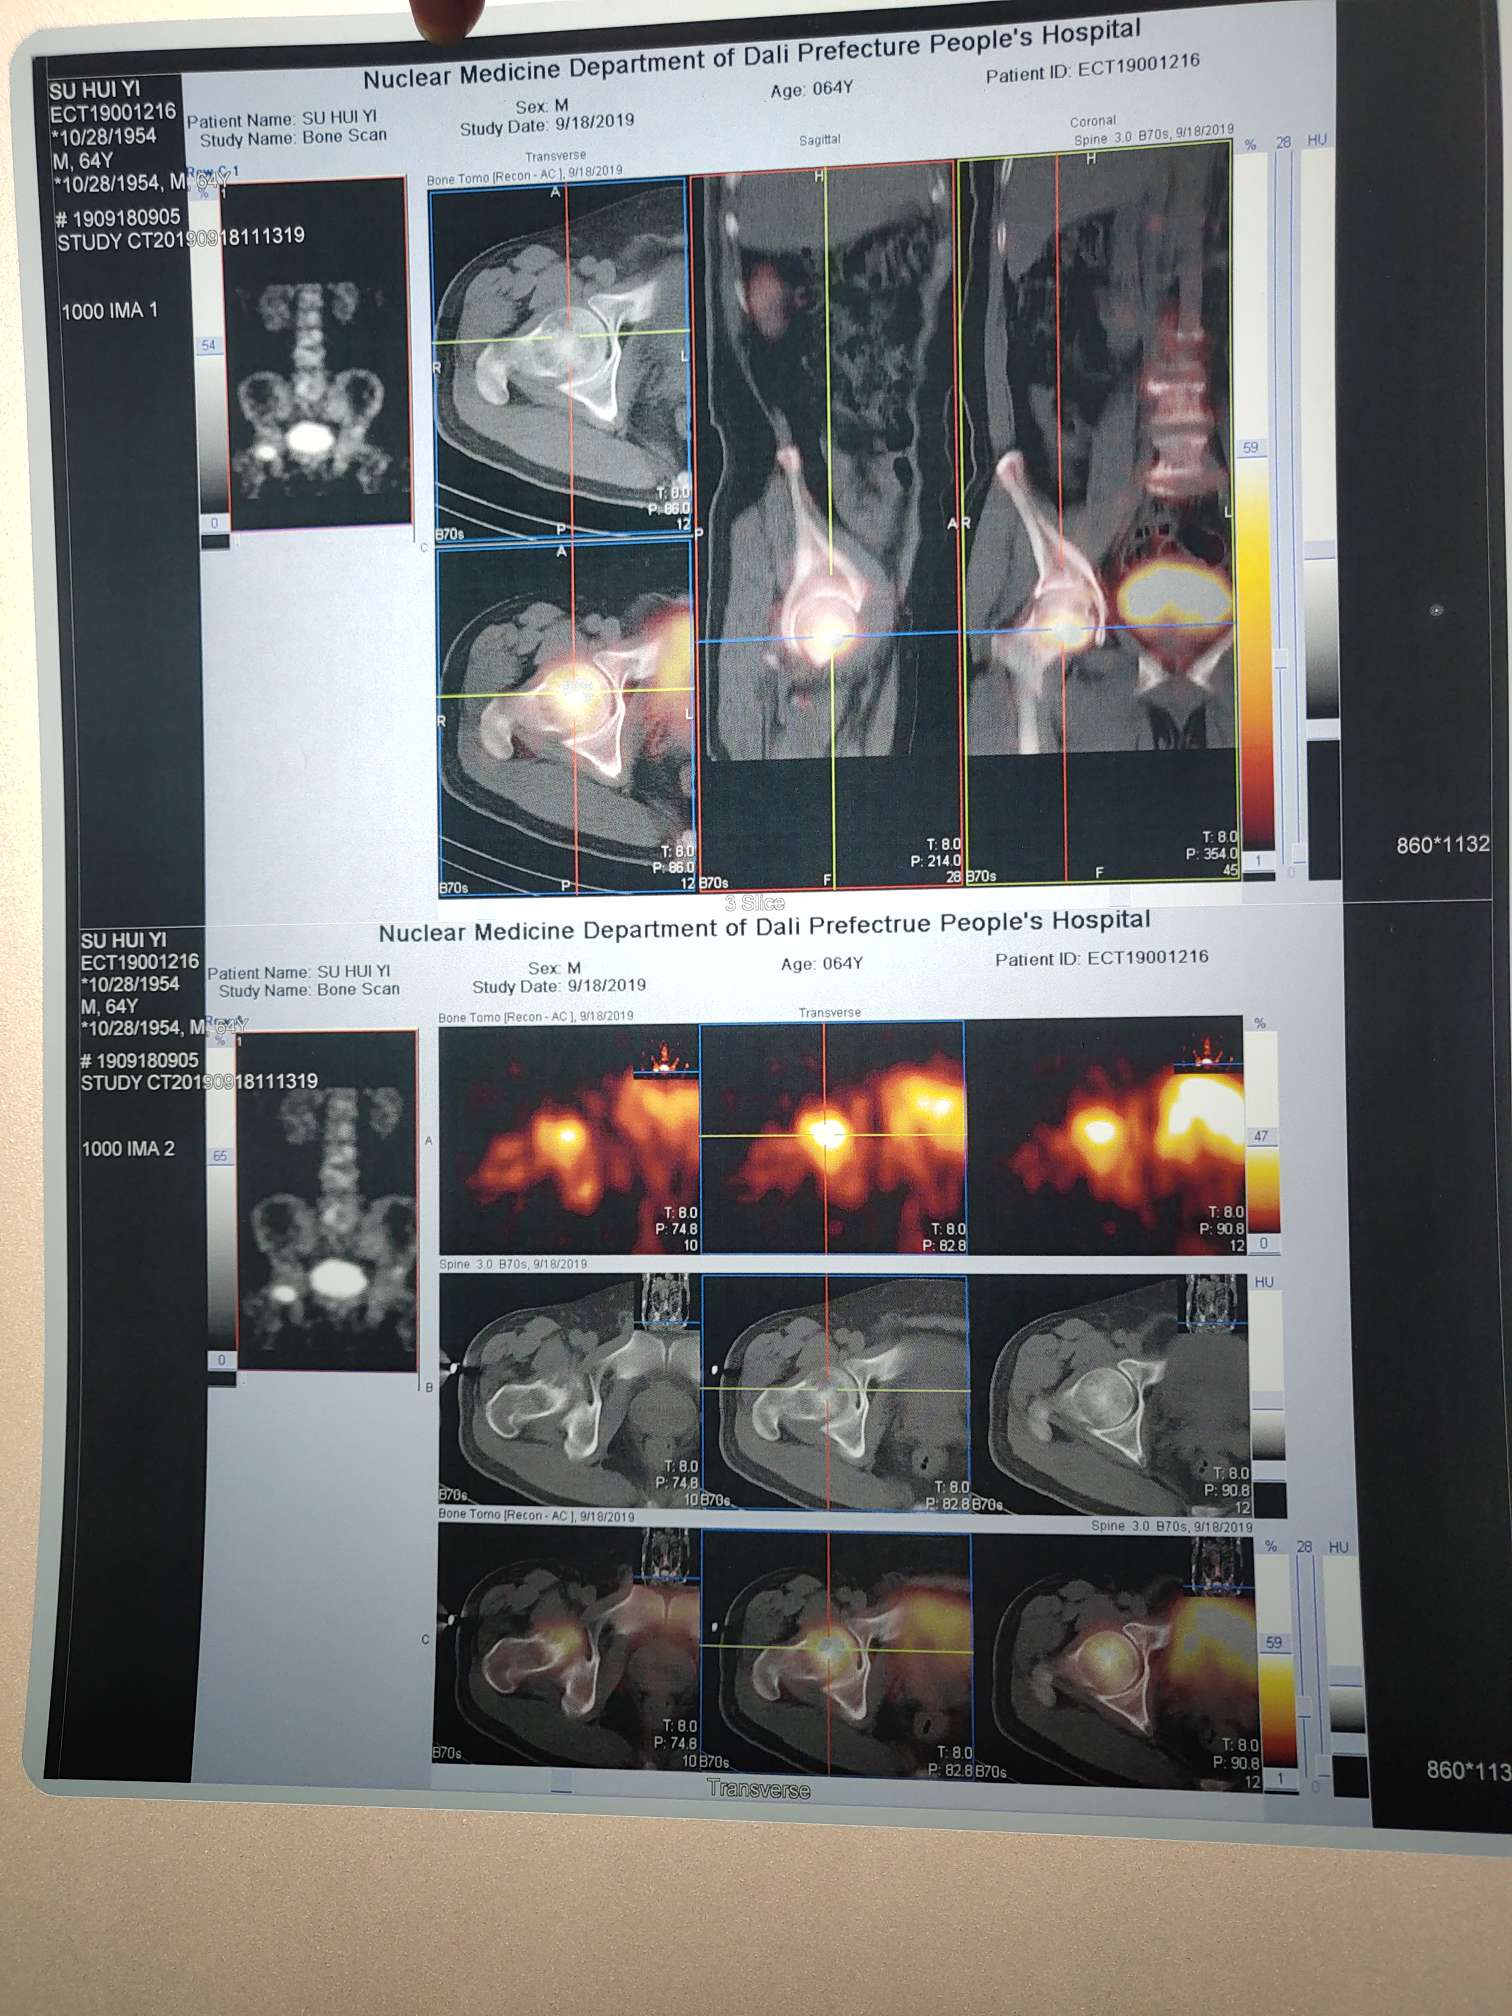

大家好!我爸爸肺癌骨转后打了进口的密固达,效果很好,这几天骨质破坏的地方疼痛缓解好多,但是由于是髋关节,走路还是影响,要用拐棍。我有几个疑惑:

1、这种情况可以做关节置换手术吗?想在他没化疗身体好时候换关节,让爸爸可以走路;

3、我爸爸气管镜没有刷到癌细胞,原发位置容易气胸就没做,直接抽血查突变和免疫,但结果还有十天才出,十天里一样不做好心慌,担心病情发展快,根据骨转在脊椎腰椎股骨肱骨想先试吃易瑞达可以吗?